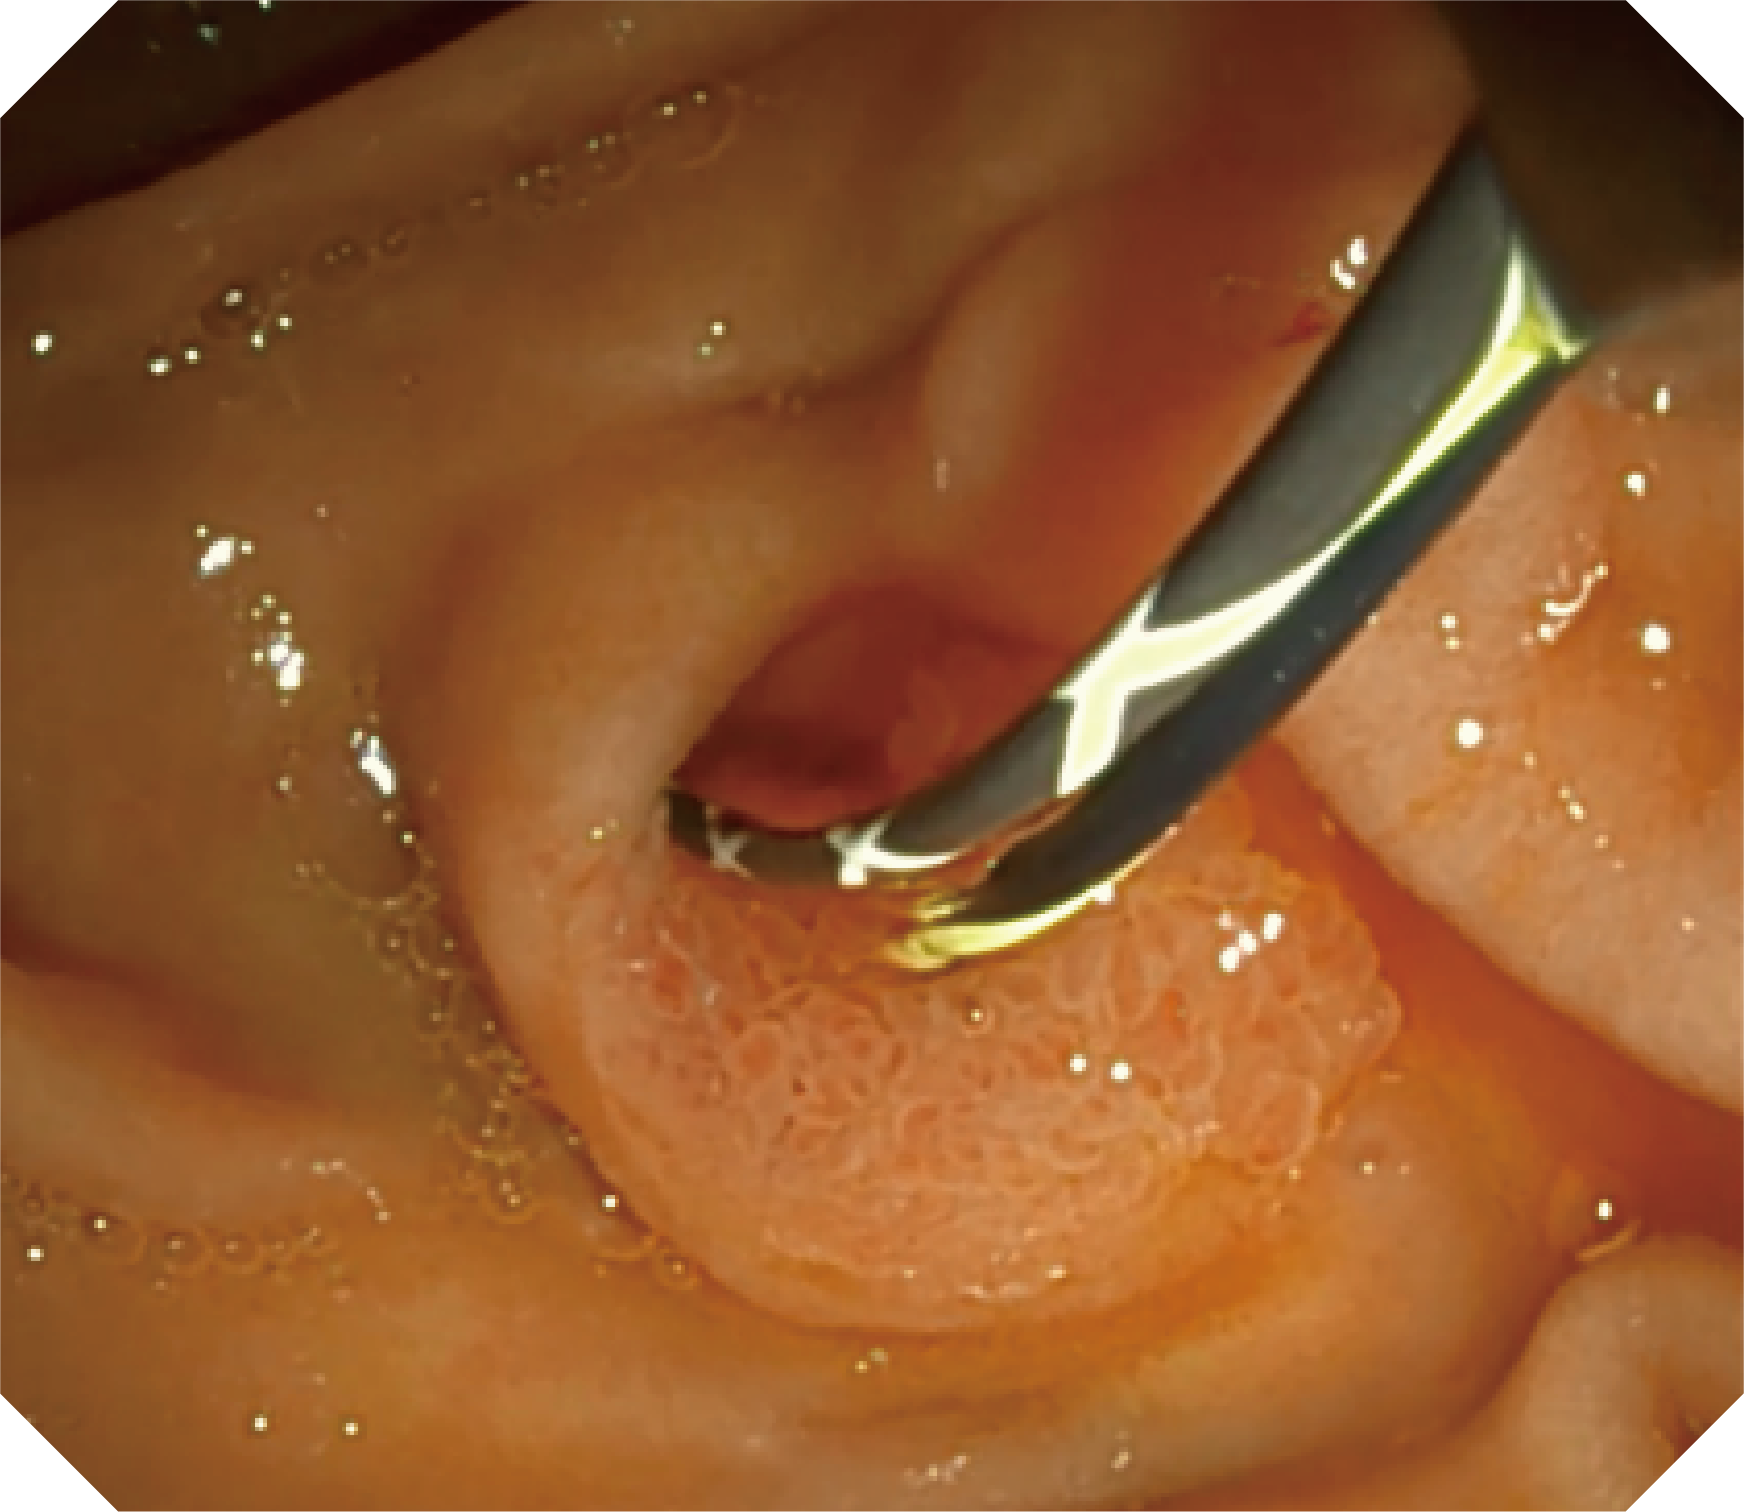

CMOS传感器提供高清内镜视野 SFI/VIST光学染色技术凸显病变区域

可拆卸先端帽

4.2mm大钳道,器械交换更顺畅

优异的手术器械抬举性

当切开刀伸出视野外时,导向面引导其回归视野